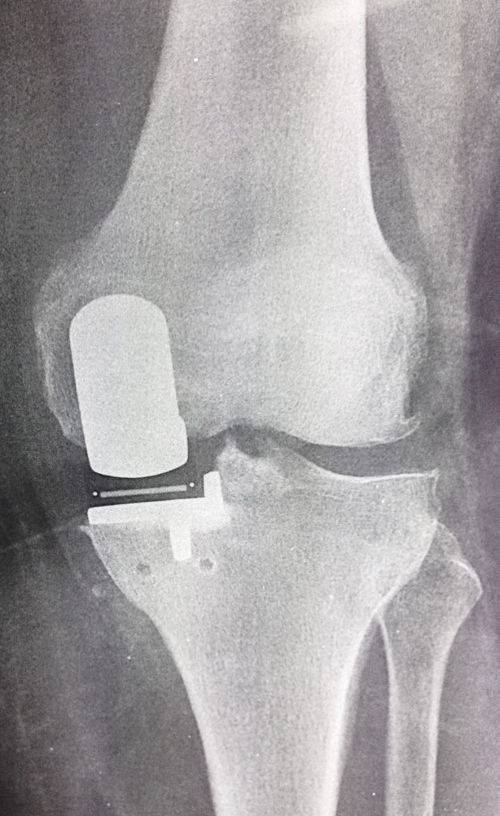

εικ. Ακτινογραφία γόνατος με Μονοδιαμερισματική Αρθροπλαστική.

Αντικατάσταση μόνο του έσω διαμερίσματος (αριστερό τμήμα της φωτογραφίας).

Δεν αφαιρέθηκε το υγιές τμήμα της άρθρωσης (δεξιό τμήμα της φωτογραφίας)